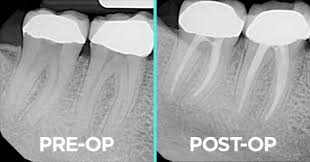

- एक्स-रे (X-ray): सर्वप्रथम दंतचिकित्सक (डेंटिस्ट) दाताचा एक्स-रे (X-ray) घेऊन जंतुसंसर्गाची व्याप्ती तपासतात.

Image source: Link.